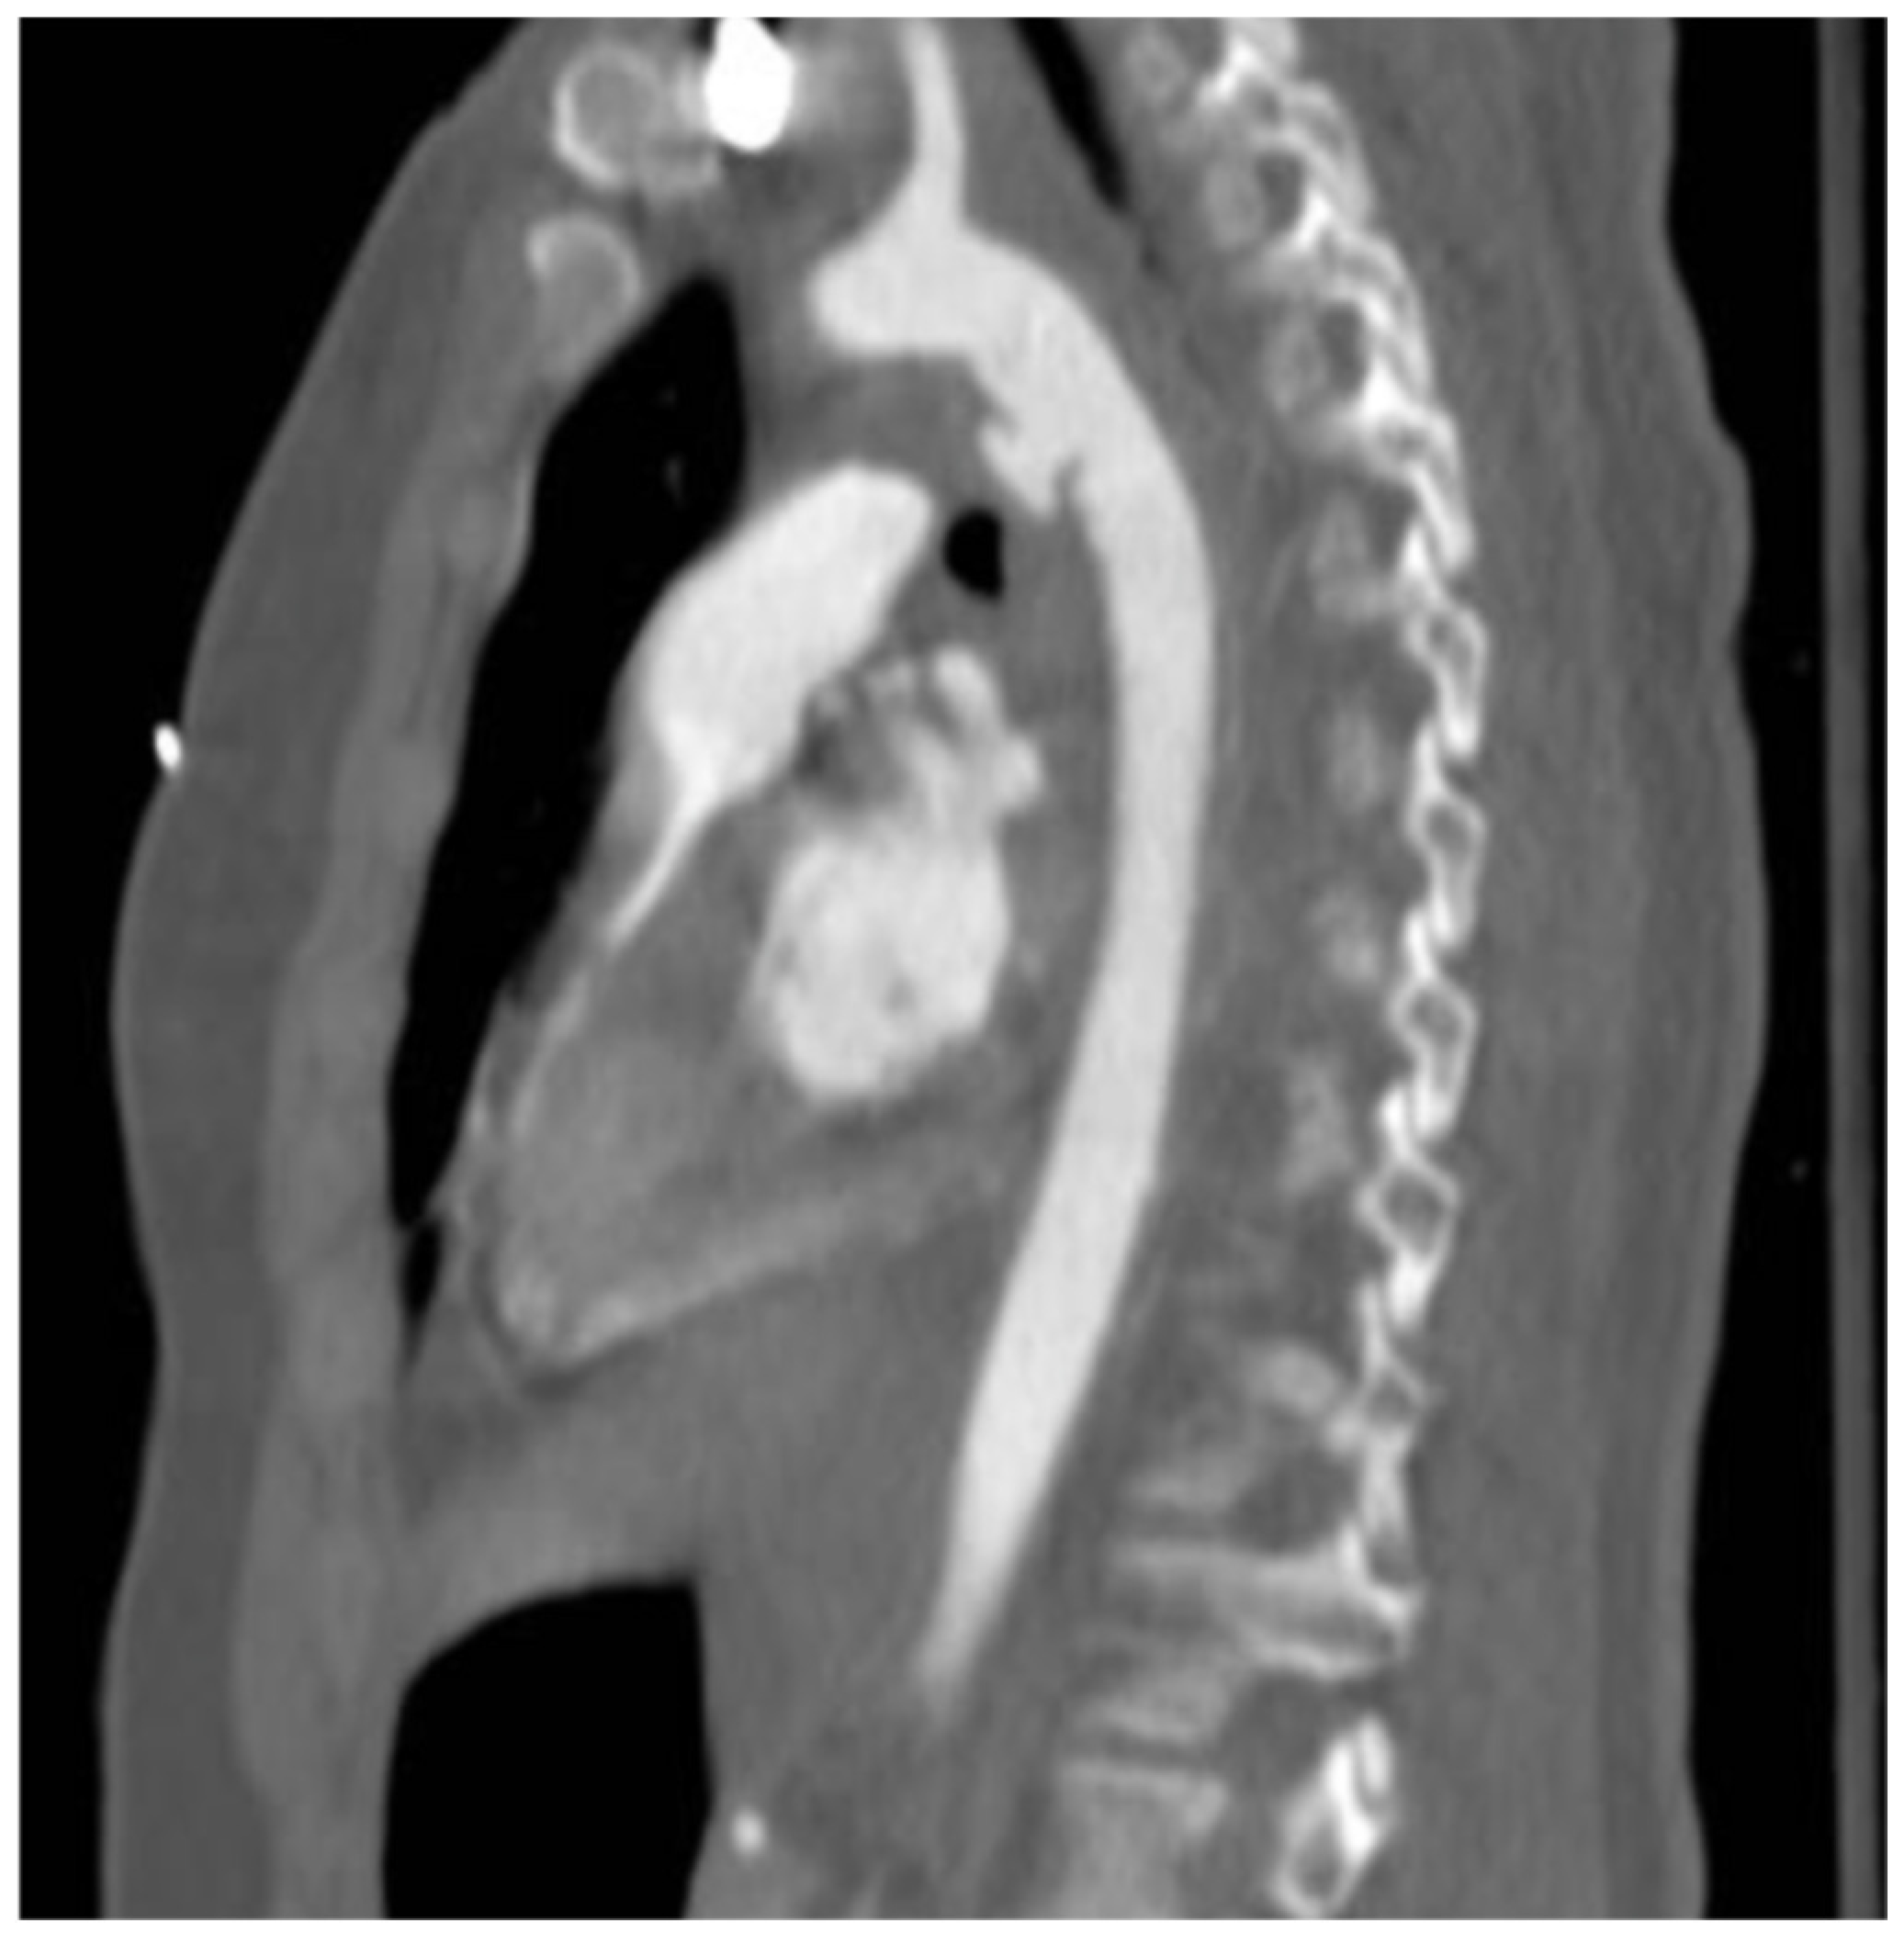

Endovascular Repair of Blunt Aortic Trauma: A Multidisciplinary Approach and a Retrospective Multicenter Study

- Type I: intimal tear

- Type II: intramural hematoma

- Type III: pseudoaneurysm

- Type IV: rupture